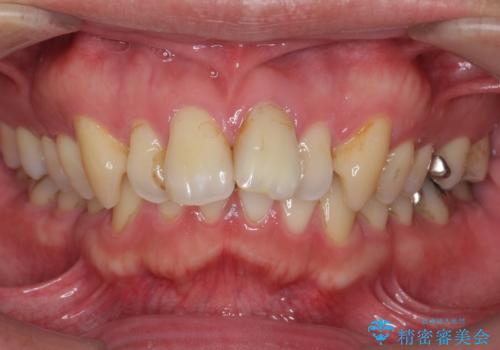

前歯が出っ歯ですきっ歯 抜かずに前歯を見た目良く

- 前歯の並びを主訴に来院。

前歯が出ており、また、左上の側切歯が1本生まれつき少ない状態でした。

また、右の奥歯の関係も上が前にある状態で大きくずれていました。

臼歯関係は無理に1級にしようとすると抜歯が必要になります。

今回は左右とも1歯対2歯の関係であるため、それは変えずに前歯を可及的にひっこめて足りない部分をブリッジで補う治療としました。

奥歯の関係を完全に1級にするには右上の小臼歯の抜歯が必要でしたが、もともと左上の前歯が生まれつき少ないため今回は歯を抜かずに治療しています。